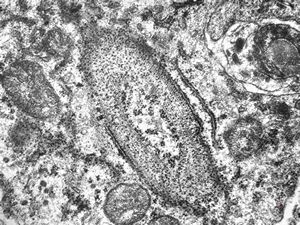

M,1y. | unusually cup-shaped mitochondria - plexus papilloma